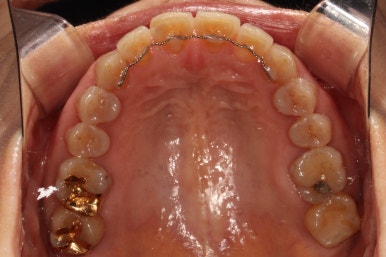

위에 보이는 사진은 교정장치를 붙이고 불과 4개월 후 입니다!

생각보다 위턱 앞니가 빨리 가지런해 진 것을 확인할 수 있습니다.

아래 앞니만 조금 더 가지런해지면... 될 것 같은 느낌이네요.

그리고 교합면 사진을 통해 전체적인 진행 상태도 파악할 수 있죠.

씹는면에서 보아도 상당히 가지런히 완성된 것을 보실 수 있습니다.

교정치료가 끝나면 혀쪽에 유지장치를 붙여드리는데요, 치석이 보다 덜 생기도록 하기 위해서 치아 표면 그대로의 모양을 따라가는 와이어를 제작하여 부착해드리고 있습니다.

조금 더 비용을 들이더라도 정성담긴 모양의 유지장치입니다!!

치아 사이 공간까지도 완벽하게 밀착하고 지나가야 좋은 고정식 유지장치입니다. 그래야 치석도 덜 생기고 관리가 편해지시거든요..

교정치료가 끝나고 2년 뒤 내원하셨을 때의 구강내 사진입니다.

스크롤을 위아래로 이동해가며 보시면 아시곘지만, 치열의 변화가 거의 없어요!

성인 앞니 부분교정 2년이 지나고 나서도 변함없이 깔끔하게 유지되고 있는 위턱아래턱 관계를 보실 수 있을거에요. 이렇게 관리 잘 해주시는 분들께 치과의사도 감사함 뿐입니다!

교정유지장치 끊어짐 없이 아주 깔끔하게 잘 관리되고 있습니다.